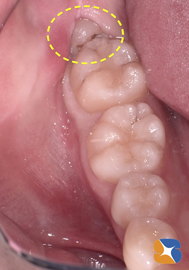

左絵は、お口の中の状態を確認したところです。

奥には手盛りで「粗雑な詰め方」をした白い歯と虫歯の穴で崩壊した親知らずの歯がありました。

女性のお口は小さいため、奥歯は特に虫歯になりやすく、治療も困難になる事が多いです。

また、親知らずが横向きに生えてきて虫歯になることが多くあります。そのため、隣りの歯に虫歯が移ることは頻繁にあるとはいえ…。 続きを読む